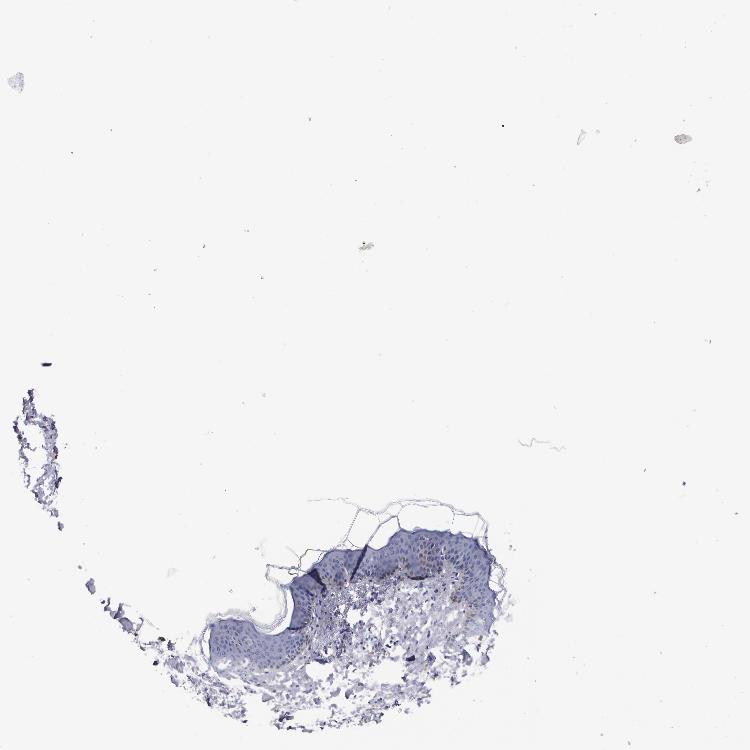

TISSUE PRIMARY DATA SKIN Show tissue menu

SKIN 1 - Antibody stainingi

Antibody staining in the annotated cell types in the current human tissue is reported as not detected, low, medium, or high, based on conventional immunohistochemistry profiling in selected tissues. This score is based on the combination of the staining intensity and fraction of stained cells.

Each image is clickable and will lead to virtual microscopy that enables deeper exploration of all samples and also displays staining intensity scores, fraction scores and subcellular localization as well as patient and tissue information for each sample.

Antibody HPA024372Antibody CAB002791

Langerhans -Not detected

Arrector pili muscle cells Not detected-

Cells in basal layer Not detected-

Cells in corneal layer Not detected-

Cells in granular layer Not detected-

Cells in spinous layer Not detected-

Endothelial cells Not detected-

Extracellular matrix Not detected-

Fibroblasts -Not detected

Fibrohistiocytic cells Not detected-

Keratinocytes -Not detected

Langerhans cells Not detected-

Lymphocytes Not detected-

Melanocytes Not detectedNot detected

Vascular mural cells Not detected-